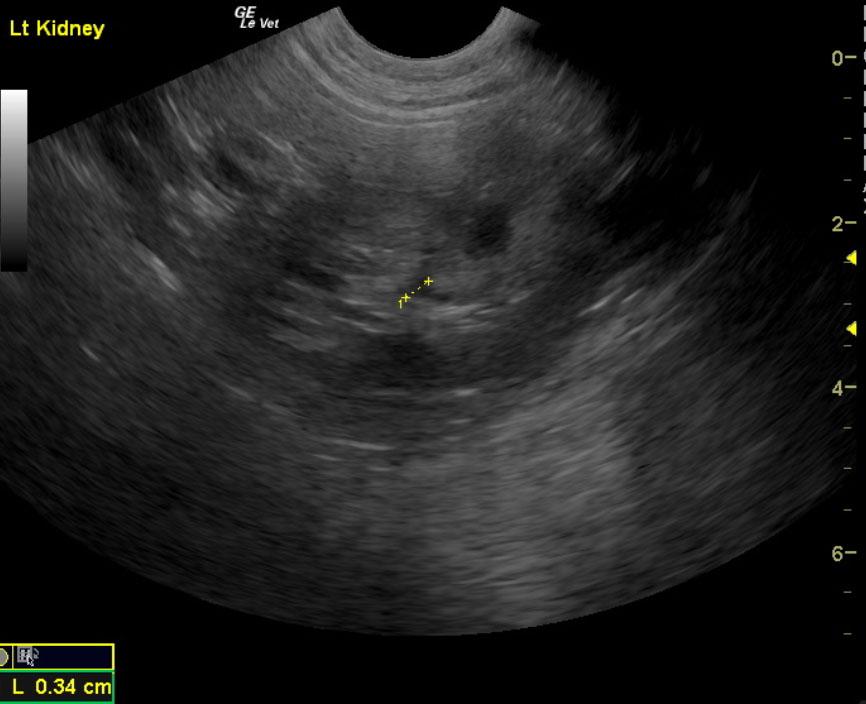

Pyelectasia could be due to scarring or persistent low grade infection or from passage of small calculi. Calculus may be secondary to chronic infection. Long-term antibiotic therapy should be considered in this patient even if the cultures are negative in hopes that the pyelectasia will completely resolve. Because a certain level of renal dysplasia could be present in this patient, BUN and creatinine evaluation should be considered as part of the work up. The persistence of white blood cells in the urine would suggest ongoing probable low grade infection. Recheck sonogram should be performed after the 4 additional weeks of antibiotic treatment.

The kidneys in this patient had a persistent, slightly irregular contour, with the left kidney demonstrating slight pyelectasia (0.26 cm). The urinary bladder, trigone and pelvic urethra presented normal wall thicknesses with anechoic urine and normal tone. The urinary bladder revealed slight calculus at 0.23cm, yet was not shadowing. No evidence of inflammatory or neoplastic changes were noted.